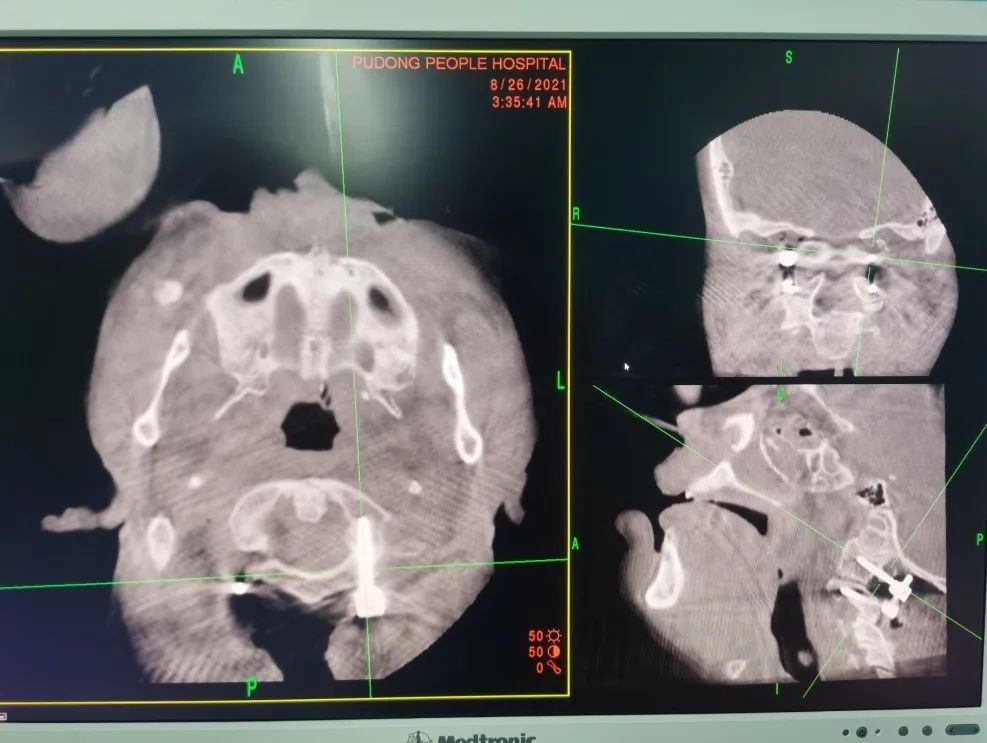

手术过程:经鼻插管全身麻醉后,在持续颅骨牵引状态下完成体位摆放、寰枢椎复位操作。在摆放过程中利用Mayfield架固定头颈,胶带将上肢固定于身体两侧,术中O-arm确认枢椎齿状突及寰枢椎得到有效复位。

患者颈后切口示意图、O-arm应用术中显露枕骨大孔周缘、寰椎后弓、枢椎棘突及椎板、寰枢椎侧块,C4棘突上放置示踪器,术中O-arm自动扫描获取寰、枢椎重建影像并传输至导航系统自动注册。

然后在导航图像引导下,在寰、枢椎选取最佳进钉点和进钉角度植入椎弓根螺钉。

内固定植入术后O-arm扫描重建图像显示C1-2椎弓根钉置钉位置精确随后弯棒固定、锁紧螺钉尾帽。